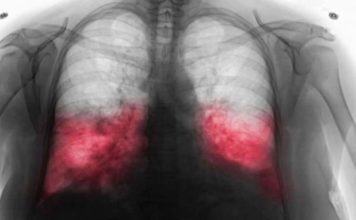

VELlKl BR0J ZARAŽENIH H0DAJUĆ0M UPALOM PLUĆA: Ako imate ove simptome 0DMAH...

Hodajuća Upala Pluća: Tiha Prijetnja ZdravljuU ovom članku fokusirat ćemo se na hodajuću upalu pluća, bolest koja često prolazi neprimijećeno, ali može imati ozbiljne...